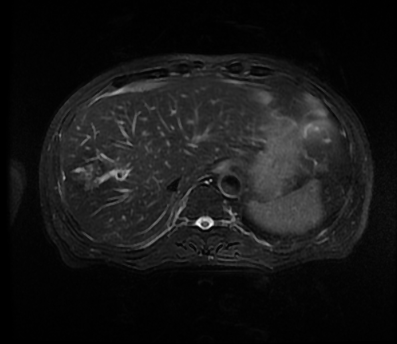

手术后

由于患者患有糖尿病,机体抵抗力较差,术后肿瘤科予以积极抗炎治疗,并邀请内分泌科刘际川主任参与会诊,在肿瘤科医护人员的精心治疗护理与内分泌科的精准降血糖治疗下,老杨身体日益康复,血糖也恢复正常。术后一个多月复查右肝的脓肿已全部消退吸收,现已经顺利拔除引流管。目前,老杨已经能跑出病房到外面遛弯了。当有人来探望他时,老杨总不忘夸赞康华医院的技术一流,而且病房的医生护士服务态度也同样一流。